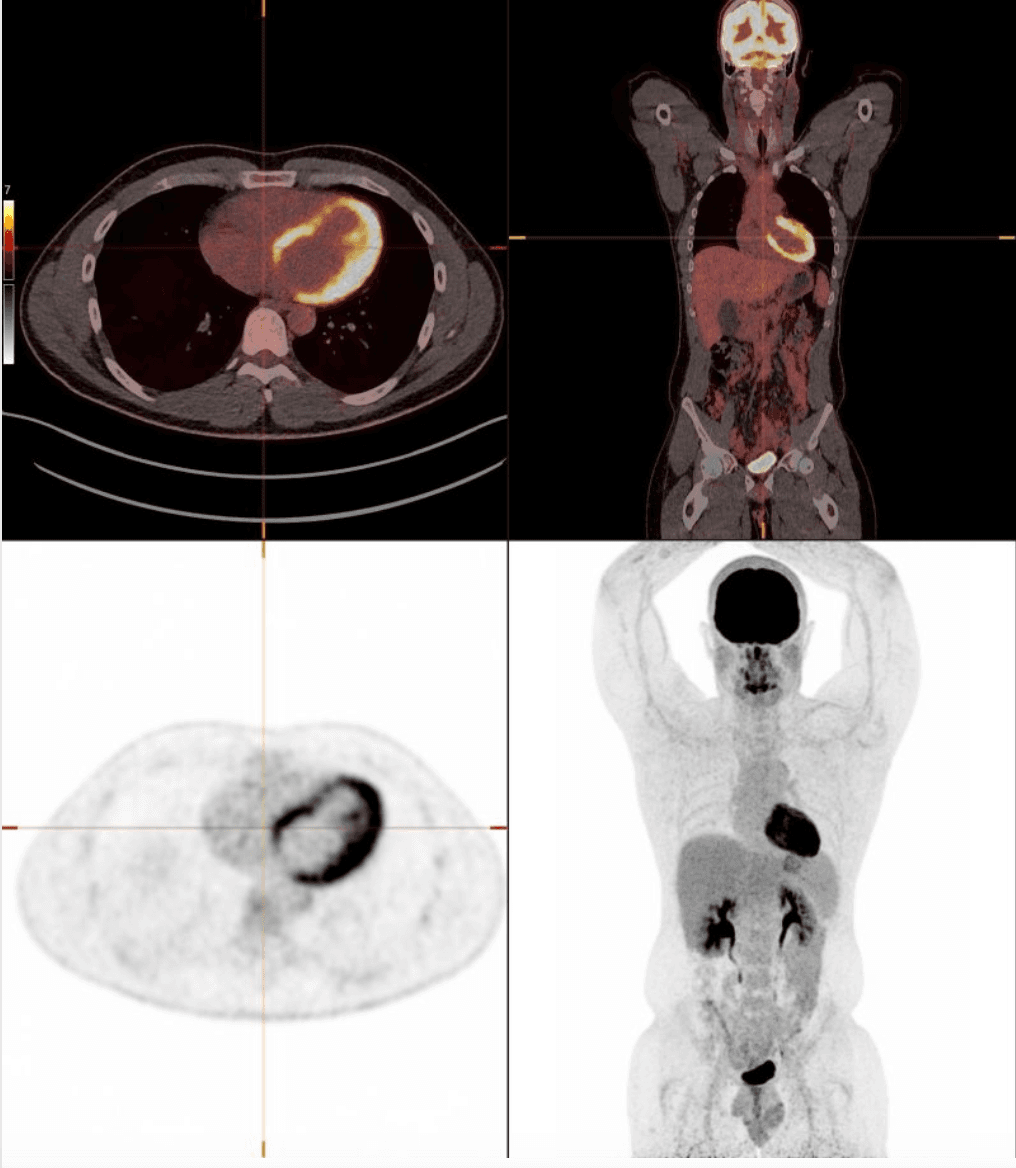

Als nucleair radioloog zie ik op PET-CT's elke dag het eindpunt van ziekte. Maar steeds vaker viel me op dat er op echo, CT en MRI een vroeg alarmsignaal zichtbaar is: leververvetting. Een marker van metabole ontregeling.

Nucleaire geneeskunde en radiologische beeldvorming, met speciale aandacht voor metabole, inflammatoire, cardiovasculaire en oncologische ziekten.